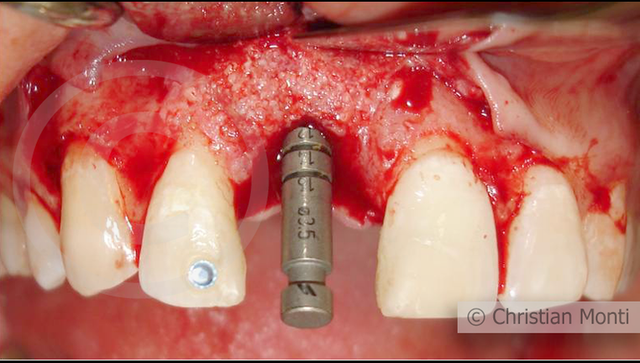

EDENTULIA SINGOLA

Impianto in sostituzione di un incisivo superiore